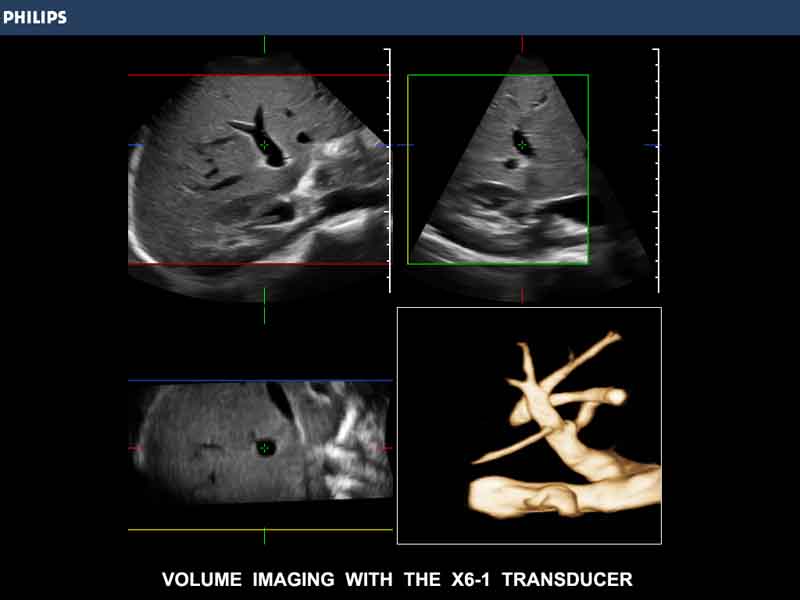

Trīsdimensionālā attēlveidošana iegūst ar vien lielāku klīnisko nozīmi diagnostikā, un X6-1 to pietuvina rutīnas izmeklējumiem vēl vairāk. X6-1 zonde ir vienīgā zonde ultrasonogrāfijas tirgū, kura ir paredzēta augstas izšķirtspējas 2D attēlošanai, sniedz papildus informāciju ar Live xPlane un nodrošina 3D/4D attēlošanu tikai vienas pogas spiediena attālumā. Pateicoties 3D iespējams vizualizēt orgānus koronālajā plaknē, izpētīt veidojumus un struktūras visās trijās plaknēs, kā arī sadalīt visu tilpumu kā tomogrāfijā ar iSlice funkciju.